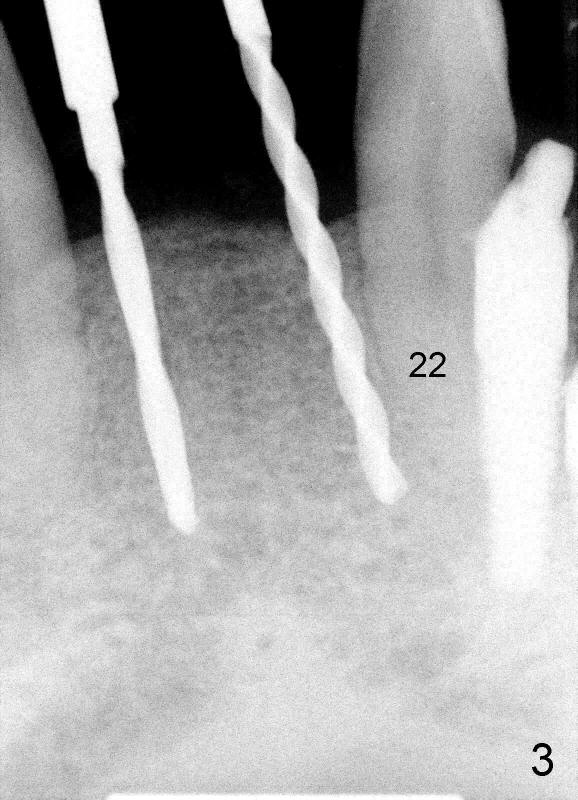

Kent has lost four of the lower incisors (Fig.1 between #22 and 27, S: stent for CT scan). It is planned to place two or three 3.0 mm one piece implants (Fig.2 axial section at root level). Intraop PA shows that one of 1.5 mm pilot drills is close to #22 (Fig.3). The trajectory of this osteotomy was then changed with difficulty; the final PA shows two of 3.0x17 mm one piece implants (Fig.4). Postop, the patient is doing fine. To get the best trajectory, we will penetrate the bone half distance of the intended length with 1.5 mm pilot drills, take PA to see how the angulation is and how close to the adjacent tooth and finish the osteotomy appropriately.